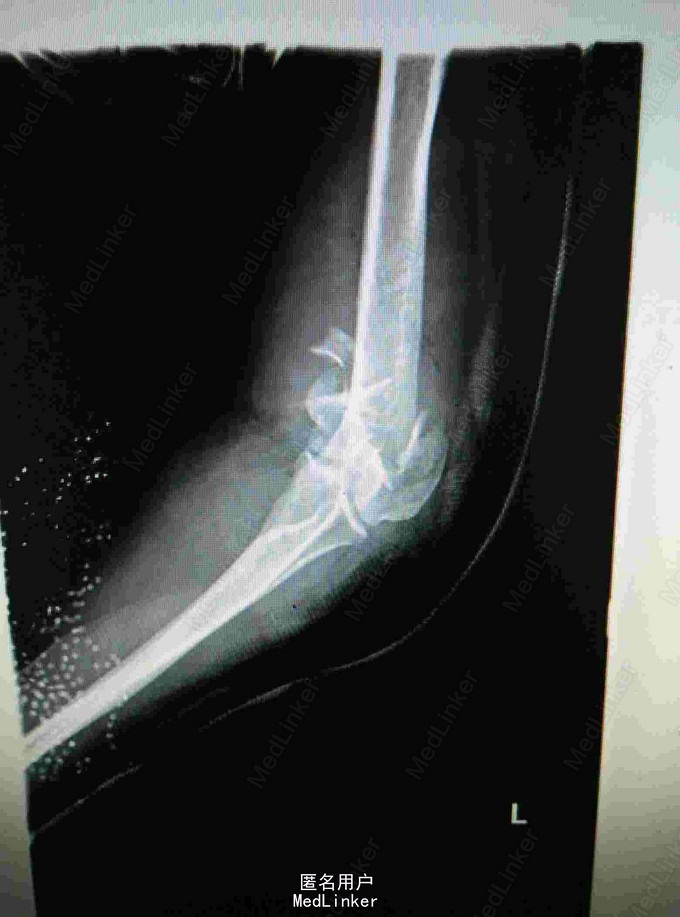

外伤致左肘关节疼痛流血,活动受限4小时 患者青年女性,因不慎摔倒致左肘疼痛流血,当即出现活动受限,肘关节可见骨外露,于当地医院行X线片提示肱骨髁间粉碎性骨折,清创包扎后入我院进一步治疗。

查体:肘关节可见骨外露,活动受限,肘后三角消失,左腕关节左拇指背伸受限,左拇指小指无法对指,五指并指困难,左手皮肤感觉减弱,以拇指小指明显 辅查:肘关节正侧位片提示肱骨髁间粉碎性骨折

诊断:左肱骨髁间粉碎性骨折 左肘关节脱位 左迟神经 桡神经 正中神经损伤 治疗:左肘关节开放伤清创术+外固定架固定术